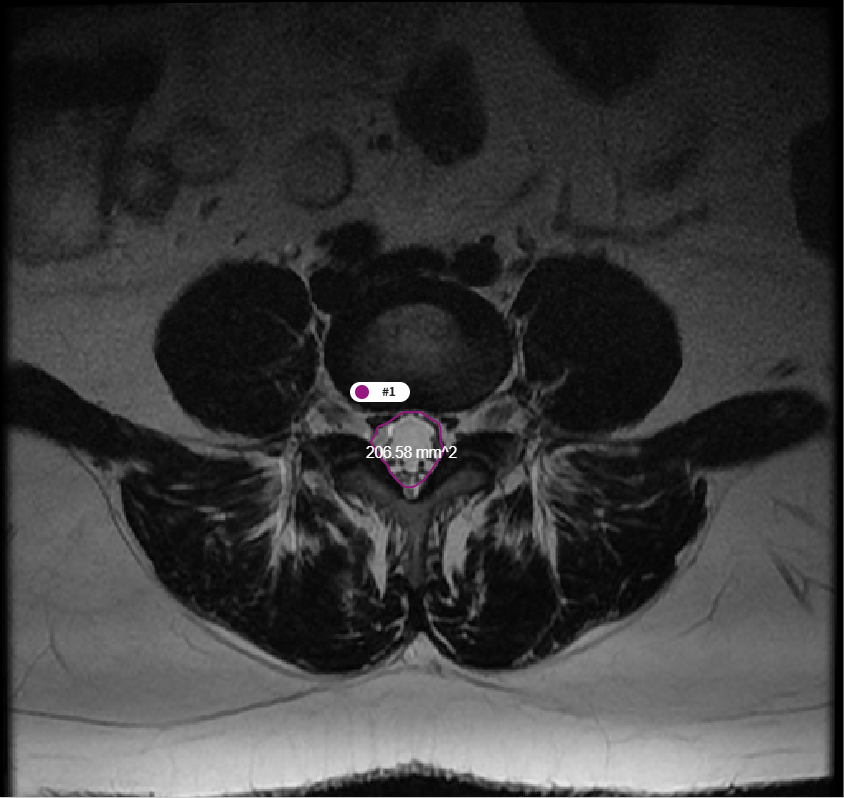

3. T2 Axial에서의 척수 영역 분할 및 면적 측정 모델

- 모델 학습

- 바이오 의료 영상 분야에서 분할을 목적으로 만들어진 모델을 사용하여 학습을 진행.

- Erode 및 Dilate, Median Blur를 이용해 이미지 후처리. Noise 및 Hole 제거

[T2 MRI에서 척수 영역 분할 모델 개요]

- 척추 면적 측정

- Dicom Header의 Pixel Spacing 정보를 통해 AI 결과에 대한 면적(mm2) 측정

[척추 영역 면적 측정]